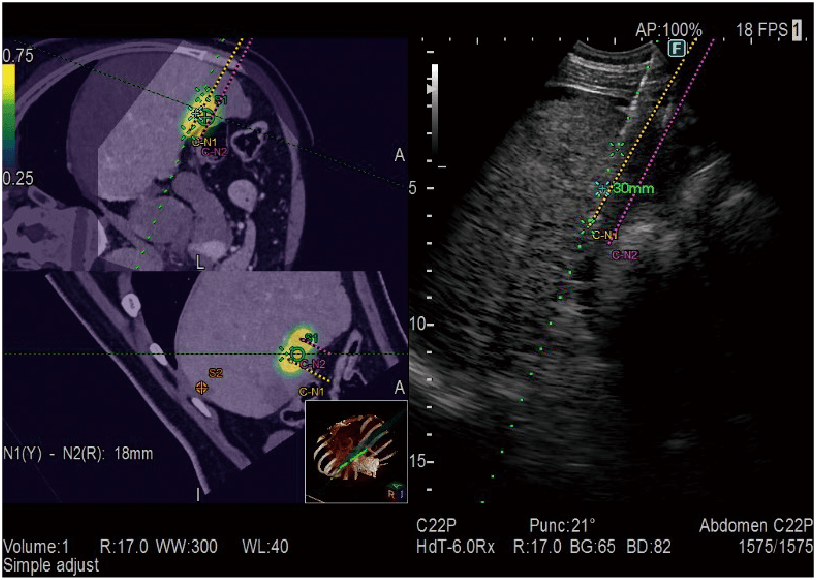

MPR images constructed from CT/MRI/PET-CT/US volume data can be synchronized to real-time ultrasound imaging. It is applied in a wide variety of clinical fields: such as for Abdomen, Breast, navigation in prostate puncture, and so on.

Provides simulation of single or multiple needle paths during navigation to a target with Real-time Virtual Sonography (RVS). The positional relationship between the marked target and needle paths can be assessed in real time using the 3D body mark and C-plane display. E-field Simulator superimposes the electric field (E-field) from the given location of electrodes on the CT image during RFA treatment. The simulation of E-field allows to consider an effective needle path.